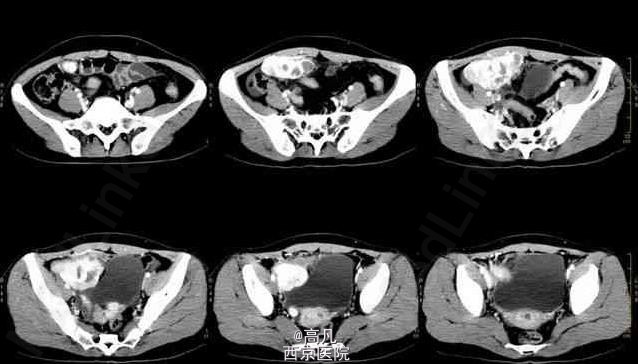

患者有周期性尿频、尿痛、血尿 辅查CT:右下腹可见囊实性不规则形肿块,实性为主。增强扫描不规则增厚的囊壁,内有多个大小不等囊变坏死区。